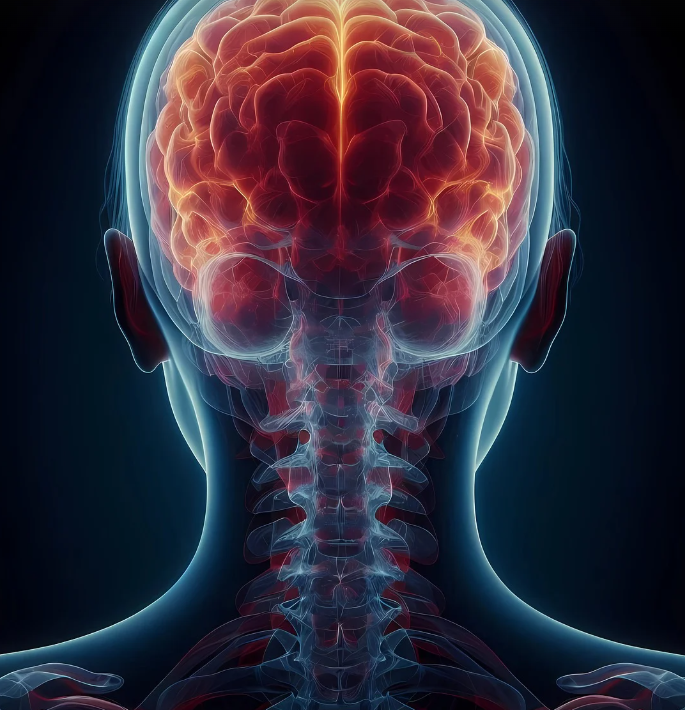

🦴 골다공증이란? 왜 위험할까요?

골다공증은 뼈의 밀도가 감소하고 구조가 약해져 쉽게 골절될 위험이 높은 질환입니다.

특히 나이가 들면서 뼈가 약해지는 자연스러운 과정이지만, 일부 요인에 의해 더 빠르게 진행될 수 있습니다.